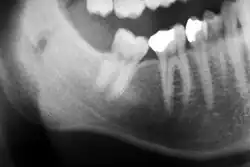

Die häufigsten Ursachen für eine Zahnwanderung sind Lockerungen der Zähne bei Parodontalerkrankungen. Oft treten diese Zahnwanderungen noch vor einer spürbaren Zahnlockerung auf. Dabei ist der Zahnhalteapparat, mittels dessen die Zähne im Kieferknochen verankert sind, bereits deutlich zerstört, die knöcherne Verankerung der Wurzeln ist insuffizient. Ein typisches Bild ist dabei die Auffächerung (Kippungen) der sechs oberen Frontzähne nach vestibulär (zum Mundvorhof hin), die durch den Zungendruck oder durch das Anschwellen parodontaler Gewebe während der aktiven Entzündungsphase nach vorne kippen.[2] Dadurch vergrößert sich der Radius des Zahnbogens und es treten charakteristische Lücken zwischen den Oberkiefer-Frontzähnen auf. Weiter gefördert wird diese Zahnwanderung durch den Druck der Unterkiefer-Frontzähne von palatinal, insbesondere bei einem sogenannten tiefen Biss. Ausgeprägte Hyperplasien, beispielsweise nach Hydantoineinnahme, können Zahnwanderungen verursachen.[3]